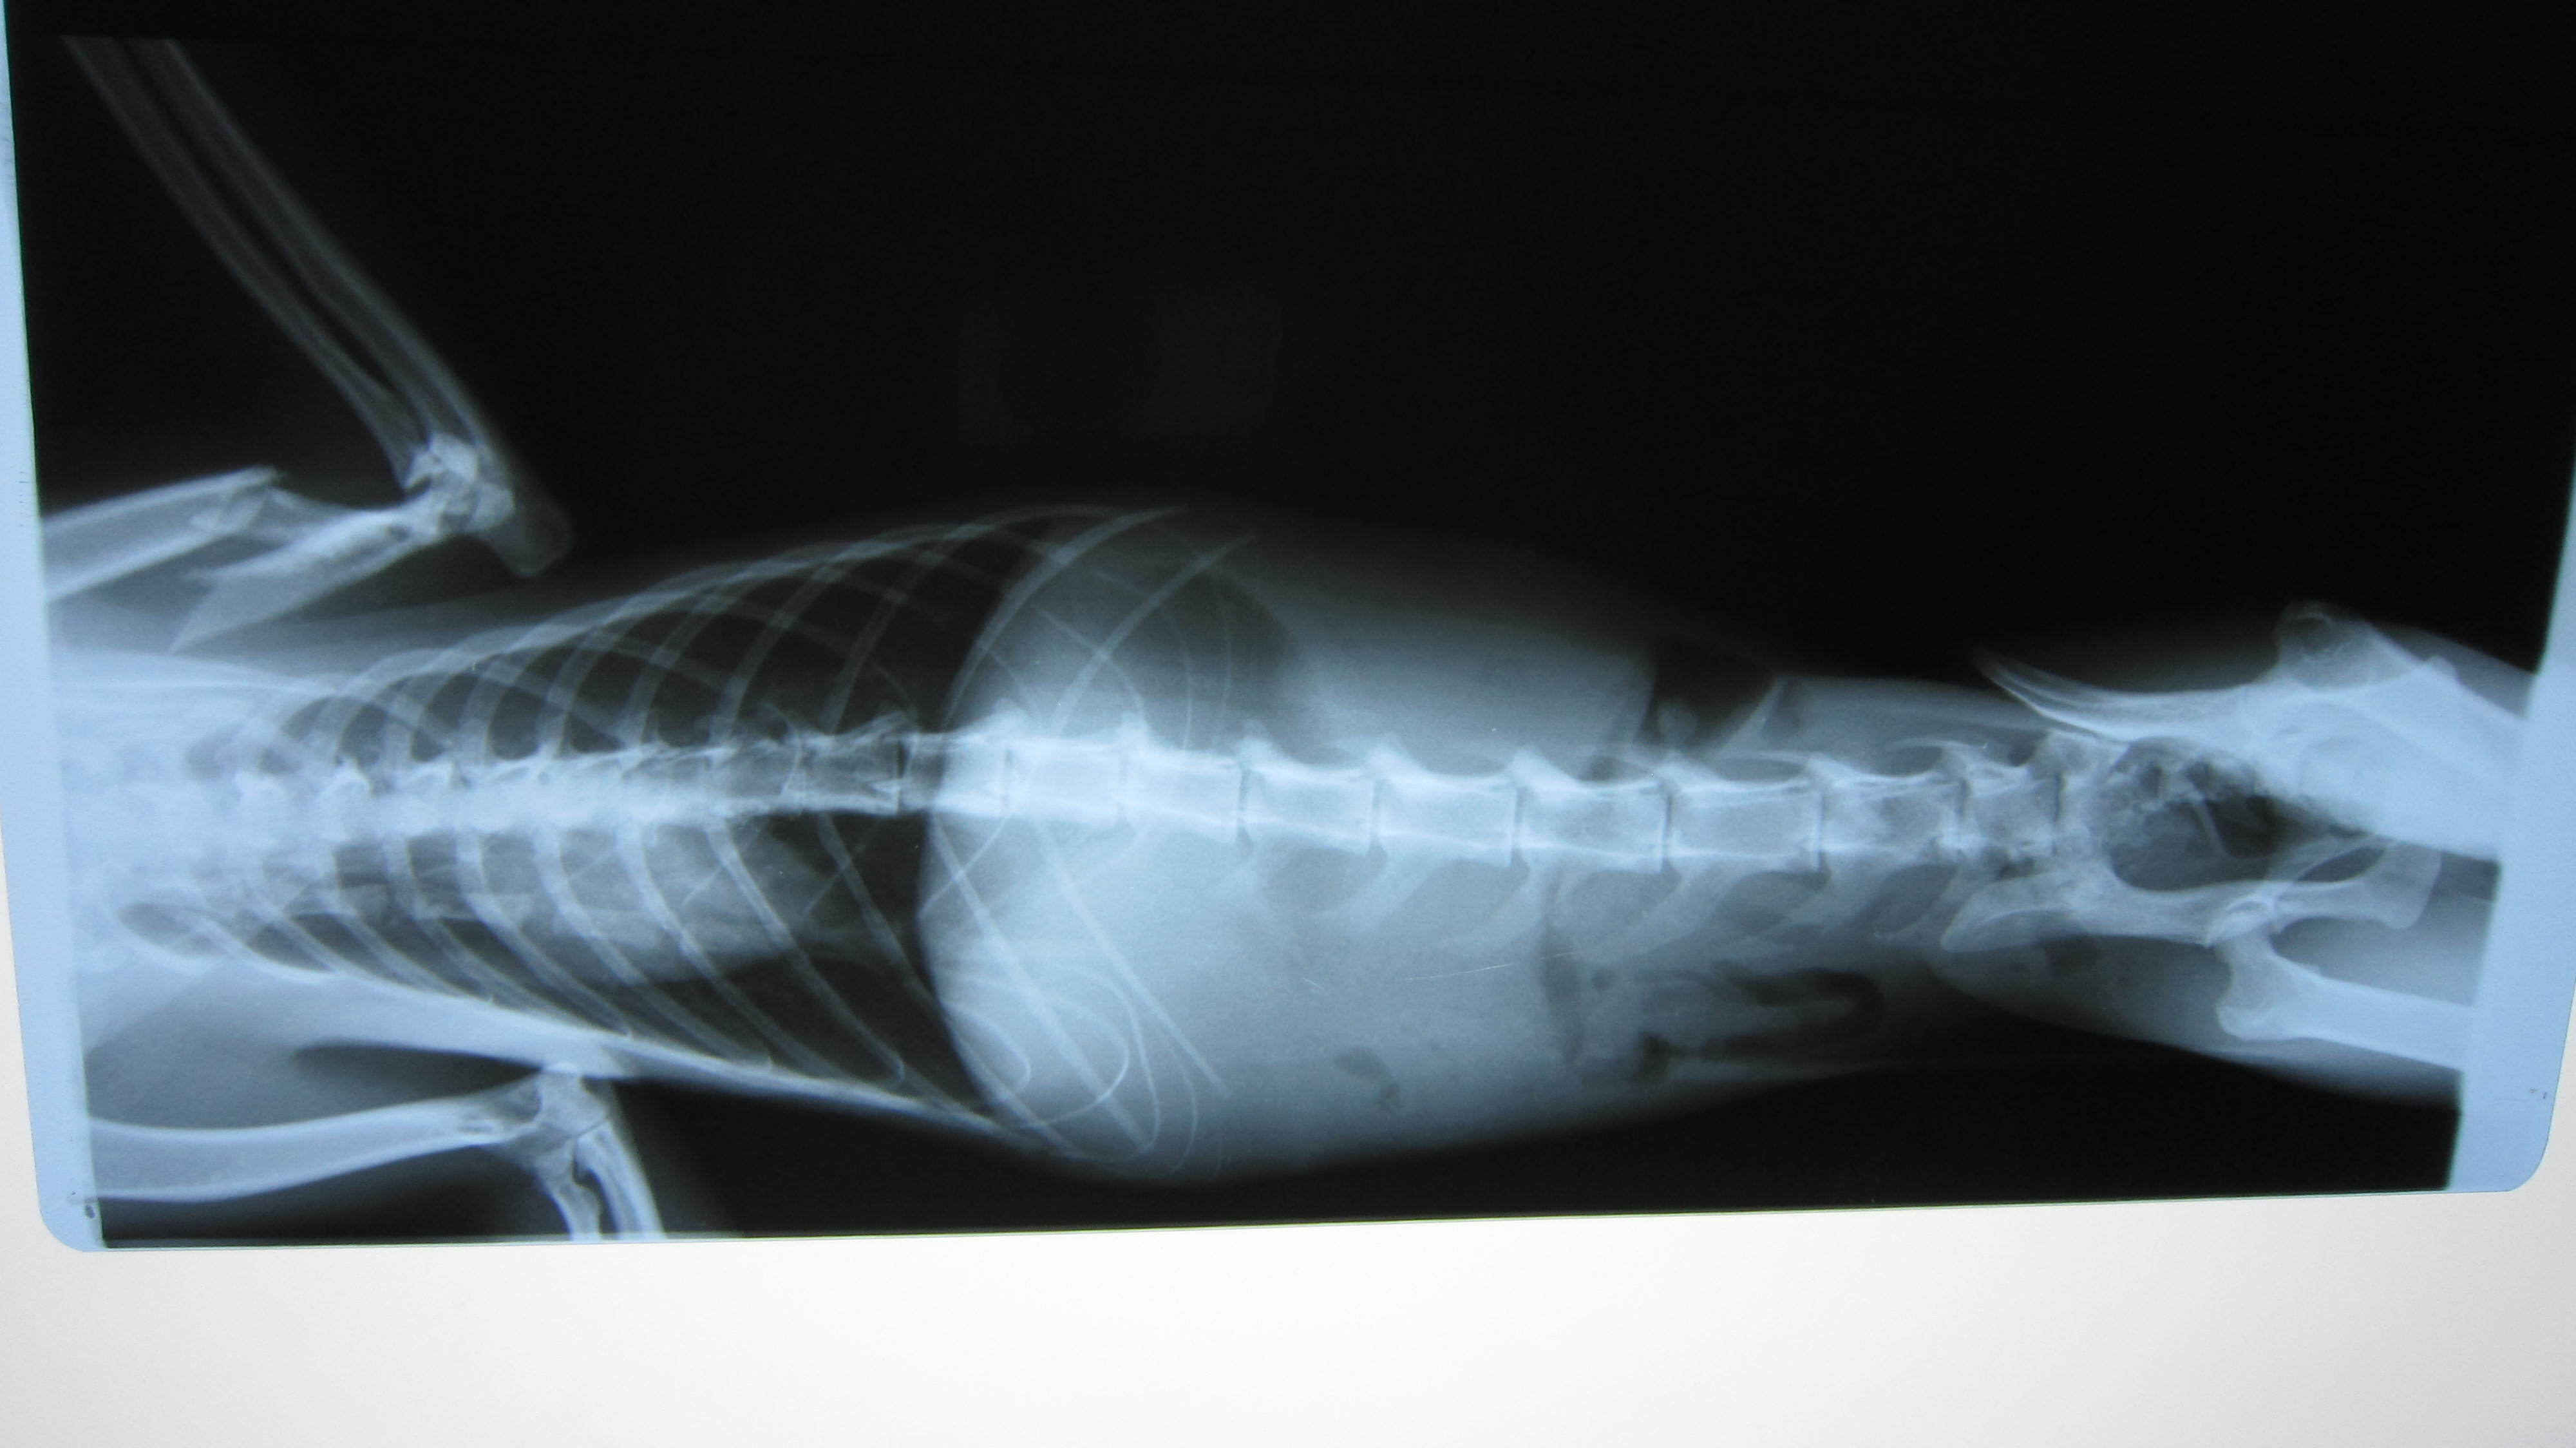

主題: 八德市大湳市場倒在路旁的斷腿貓 申請者姓名: 李明明 花色: 申請日期: 2013-05-14 22:09:32 申請者部落格: 申請者臉書網址: 所在縣市/合作醫院: 桃園縣/綠光動物醫院 治療費用: 4200元 需求人數: 10人 已結案 (2013-06-27 13:14:31) 報名人員: csaoesc x2(已付款)、Tetsu(已付款)、比比(已付款)、蔡釋慧(已付款)、Vavina Kim(已付款)、Sunny Chen(已付款)、Melody Wu x2(已付款)、swatchtw(已付款)、 候補人員: 動物病情說明: 4/26中午接獲市場賣菜阿姨通知:有一隻貓咪斷腿爬行了20多公尺,體力耗盡,倒在路旁待救援,後腿無法站立趴在地上,經通知協會後送往桃園市綠光動物醫院就醫,經X光檢查確定左前肢骨折,脊椎腔挫傷受擠壓導致後腿無法站立,醫生建議先住院以類固醇治療5~7天,觀察脊椎腔受傷及前後肢恢復程度,再決定後續治療方式,因此,初步估計醫療費用約為7千元(無須手術)至5萬元(須手術).由於目前已照顧兩隻受傷/生病浪貓,經濟上無法再行負擔,因此申請協會醫療補助. 動物近況說明: 5/9 PM16:00已由桃園綠動物醫院轉至協會安排的台北光長青動物醫院接手後續治療 (取名:馬太),骨折與韌帶受損部分以限制活動等待受傷部位自然癒合,癒合後也將影響未來的運動能力,會降低競爭力(不適合野放);愛滋/白血 無檢出;血檢有輕微貧血(營養不足)現象;左後腳背傷口須加強清創。(5/12) 有癲癇發作一次,目前繼續觀察中。

左前肢雖骨折但已能稍微站立,恢復情形較佳;後肢因關節韌帶受損、腳背傷口清創&肌肉腫脹,恢復較緩慢。

目前整體恢復情況還算不錯。